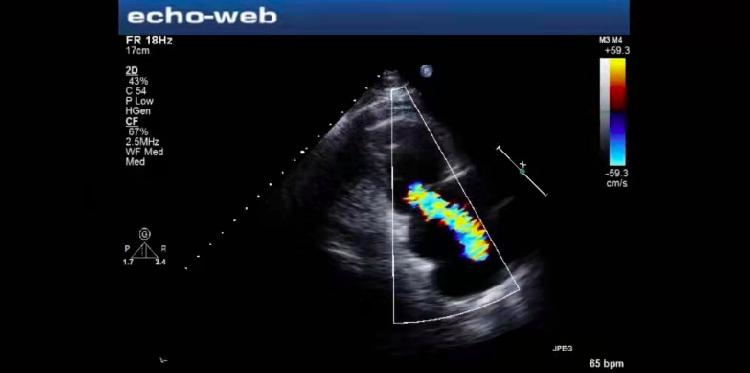

一周前,周先生到重庆出差,第二天他开始偏头痛发作,以为忍忍就好,周先生准备坚持到工作结束返程回家后再去医院就诊。但忍到第四天,症状愈发严重,疼痛时眼睛发黑,休息后稍微缓解一点,但恢复后视力仍旧模糊,一直要四个多小时后才能好转。担心脑部有损伤,周先生立即到重医附二院神经内科就诊,神经内科宋敏博士接诊后仔细问诊,患者除了明显的头痛,视力也有模糊的表现,而且有过一过性的右手麻木。考虑患者很可能发生了短暂性脑缺血发作,马上安排周先生进行了CT和核磁共振检查发现。结果表明周先生“左侧颞枕叶交界区近期皮层下小梗死可能”,但“脑MRA检查未见明显异常”,简单来说,就是发生了脑梗塞,但脑部却找不到发病原因。既然不是直接脑血管的问题,那脑梗塞的原因在哪呢?考虑患者年轻,而且有过偏头痛病史,宋敏博士高度怀疑是卵圆孔未闭导致的异常栓塞,于是进一步进行经颅多普勒发泡试验以及心脏彩超声学造影等检查,确诊周先生存在卵圆孔未闭,于是转到胸心外科进行卵圆孔未闭封堵术。

而在确诊检查和手术中又需要超声科的全力协助。通常检查卵圆孔未闭的常用方法是经颅多普勒发泡试验、右心声学造影以及经食道彩超等。其中,经经颅多普勒发泡试验无创且检出率可以达到90%以上,而经食道超声配合发泡试验是检测卵圆孔未闭的金标准。最后确诊后再由胸心外科团队在超声下或者X线透视实施卵圆孔未闭封堵术。